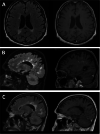

Figures